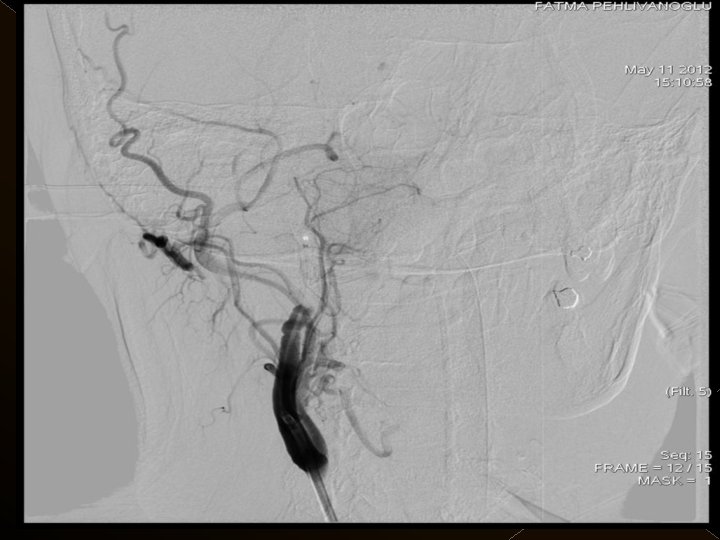

� 25 hasta (16 K, 9 E) , 27 vaskuler okluzyon � 16 orta serebral arter (MCA), � 6 baziler arter ve � 5 internal karotis arter (İCA) düzeyinde olmak üzere � Toplam 25 hasta, 27 tıkanıklığa (6 sı hariç) iv tpa sonrası endovaskuler yolla müdahale edildi

Acil servise başvuru süreleri: 1 -4. 5 saat Başvuru sırasındaki ortalama NIHSS skoru: 23 25 hastanın 21’inda kontrol serebral anjiografide tıkanıklığın tamamen açılmış olduğu görüldü. � Baziler arter ve ICA tıkanıklığı olan 4 hasta kaybedildi. � 19 hastanın 16’sında NIHSS skorlarında işlem sonrasında 24. saatte yapılan klinik değerlendirmede ortalama 10 puanlık düşüş saptandı. � � �

� İnme tedavisinde iv tpa uygulamasını takiben � intraarteriyel (İA) trombolitik tedavi (ia tpa ve ia mekanik trombolizis) � İA stent yardımı ile trombektomi yöntemleri kullanılarak tedaviye cevap ve komplikasyonlar araştırıldı.

KOMPLİKASYONLAR Ponksiyon bölgesi komplikasyonları � Trombektomi stentine ait komplikasyon (*1) � Diseksiyon(*2) � Karotikokavernöz fistül (‘ 1) � Hemorajik komplikasyonlar(‘ 5) Semptomatik-nonsemptomatik � İskemik komplikasyonlar (3) � Reoklüzyon (2 i. a) � Kontrast madde nefropatisi �